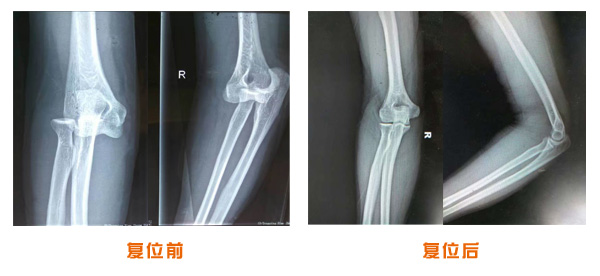

肥城市安駕莊梁氏骨科醫(yī)院是一所以梁氏手法正骨配合膏藥為特色的現(xiàn)代化專科醫(yī)院。

梁氏骨科術始創(chuàng)于清雍正年間,歷經八代,至今已有三百年歷史。據(jù)1929年泰安縣志載“梁瑞圖先生,字增生,號蓮峰,安駕莊人,精岐黃并發(fā)明接骨,凡跌打車凡跌打車軋皮不破而碎骨者......【詳細】 |